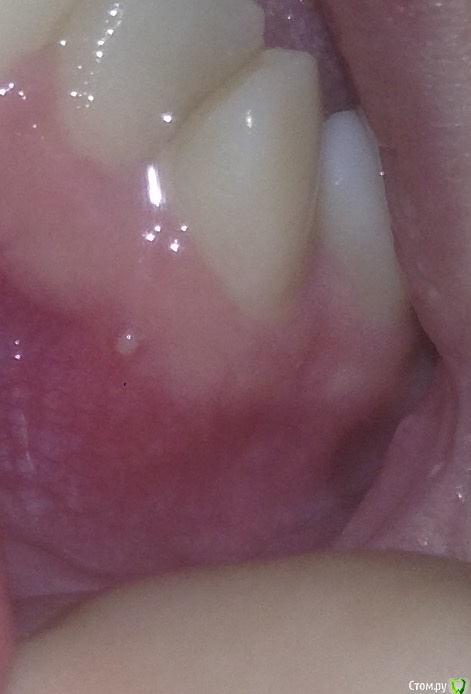

Юл1. Опубликовано 19 мая, 2020 Поделиться Опубликовано 19 мая, 2020 Здраствуйте, в хирургии была тема, но хотелось бы ещё мнения послушать. Случайно обнаружили в феврале этого года такой зуб, клиник много посетила, никто лечить не берёт. Две недели назад образовался прыщик, лопнул вчера, сейчас нет ничего, мазала метрогилом и полоскала хлоргексидином. Кт делала, ничего там особенного нет, не могу показать, не умею. Зуб абсолютно не болит. Интересует что это за прыщик был? Свищ? Бессимптомный периодонтит? Спасать зуб не буду, все в один голос говорят что шансов нет лезть в канал. Буду удалять если сломается. Вот что тогда делать? Имплант не встанет, брекеты финансово не смогу поставить, мост не хочу. Есть ли ещё какие варианты протезирования пусть даже не очень надёжного? Ссылка на комментарий

St. Опубликовано 19 мая, 2020 Поделиться Опубликовано 19 мая, 2020 Спасать зуб не буду, все в один голос говорят что шансов нет лезть в канал Учитывая вашу скученность зубов, я бы спасала. Шанс не очень высокий, но продлить зубу жизнь можно. Интересует что это за прыщик был? Свищ? Да Ссылка на комментарий

Юл1. Опубликовано 19 мая, 2020 Автор Поделиться Опубликовано 19 мая, 2020 (изменено) Действительно свищ, опять набралось, записалась к врачу, будем что то решать. Изменено 19 мая, 2020 пользователем Юл1. Ссылка на комментарий